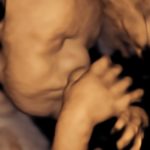

4D/5D/HD Ultrasound Gallery

Gallery